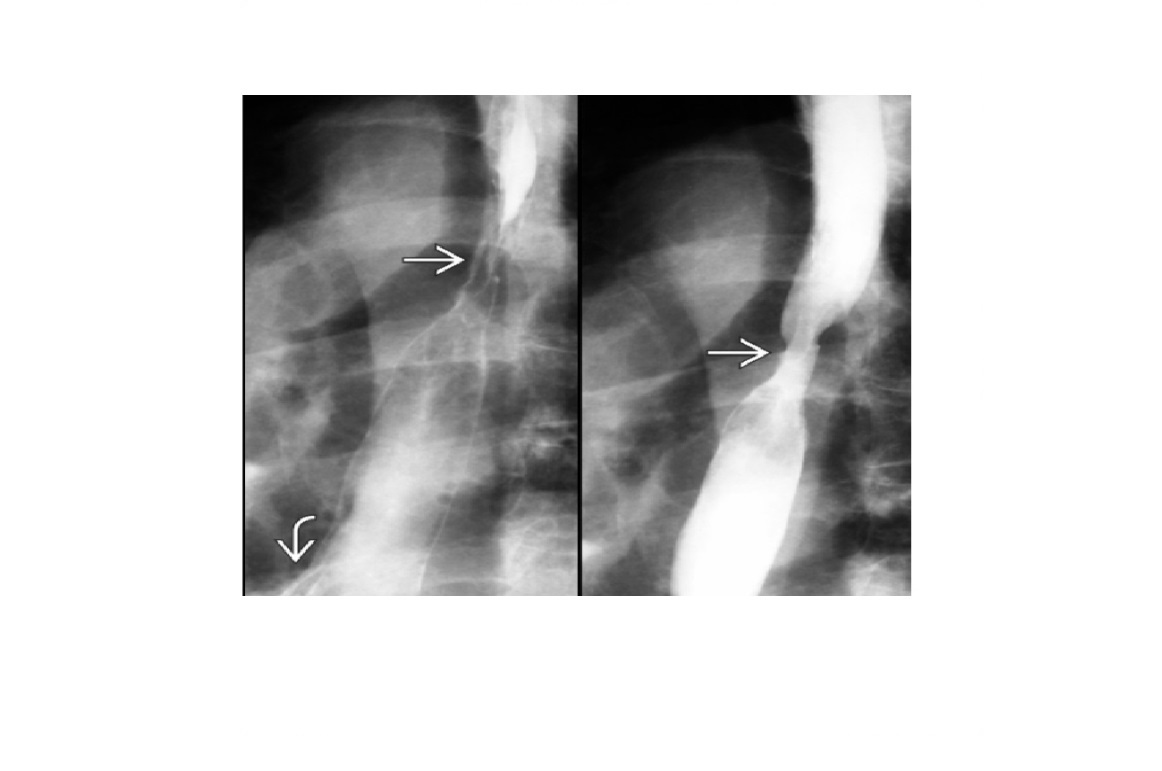

oesophageal scleroderma

-affects the Lower 2/3 (smooth muscle) with atony and peristalsis that begin caudally and moves cranially.

-Moderate dilatation of esophagus with fusiform stricture at lower end

Nb upper 1/3 to above aortic arch is normal (striated muscle)

Achalsia

- Grossly dilated whole oesophagus with smooth, beak-like tapering at lower end

Reflux Esophagitis (With Stricture)

-Longer tapered distal stricture

-Less luminal dilation

-Distinguished from scleroderma by normal peristalsis

Esophageal Carcinoma

-Abrupt proximal borders of strictured segment (rat tail appearance)

-Mucosal irregularity, shouldering, mass effect